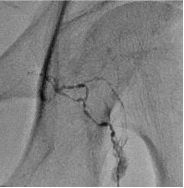

5. 一旦碘油到第三腰椎水平,等待碘油自己上升(Progression of Lipiodol up to L3,Wait for spontaneous Lipiodol progression)

如果没有发现乳糜池显影,改注射盐水1ml/5min 病例:乳糜胸